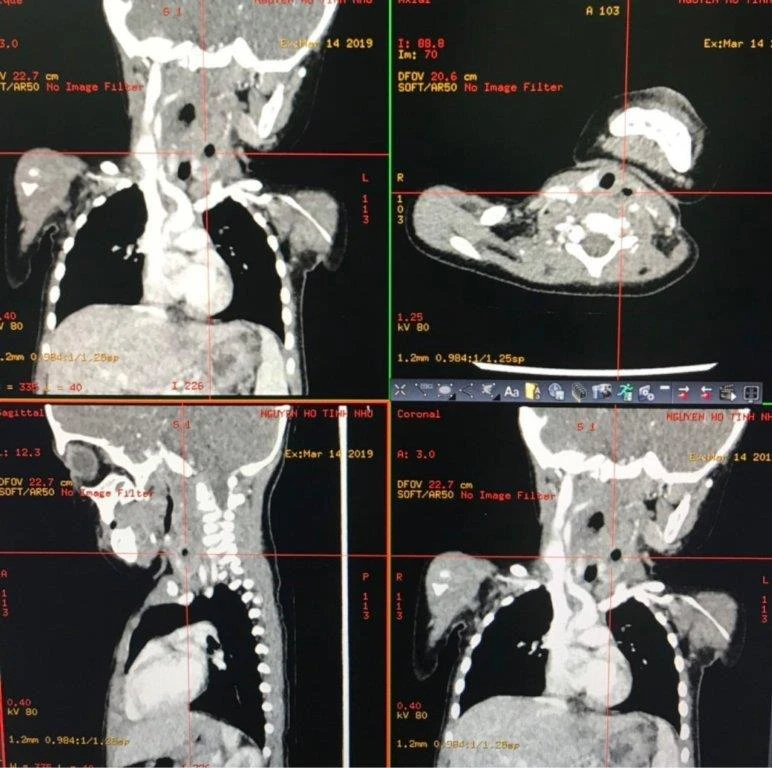

Sau 2 ngày điều trị, bé sốt cao liên tục, không thấy cải thiện nên các bác sĩ đã liên hệ chuyển Bệnh viện Nhi Đồng Thành phố. Tại đây, bác sĩ trực tai mũi họng ghi nhận bé tỉnh, quấy khóc, sốt cao, vùng cổ trái sờ thấy 1 khối mềm 2x3cm, họng đỏ, sạch, thành sau họng hơi sưng nề, chảy nước miếng nhiều, không thấy mủ, loét trong họng và tiến hành xét nghiệm máu khẩn, chụp CT scan vùng cổ.

Kết quả máu bị nhiễm trùng nặng, có nhiều ổ áp xe lớn tụ mủ, sinh hơi ở thành sau họng, chiếm hơn 2/3 thể tích của vùng cổ.

Ngay lập tức bé được chích thuốc, làm các xét nghiệm tiền phẫu, chuyển vào phòng mổ cấp cứu. BS CK2 Bạch Thiên Phương trực tiếp mổ cấp cứu cho bệnh nhi cho hay ekip đã chọc hút khối sưng nề ở phía sau trụ amidan bên phải khoảng 50ml mủ xanh đục. Quan sát trên hình ảnh CT scan, khối u lan xuống khoang cổ sâu bên trái, giữa tuyến giáp trái và các mạch máu lớn vùng cổ nên các bác sĩ quyết định phẫu thuật mở cạnh cổ để dẫn lưu hết mủ, nạo sạch mô viêm quanh tuyến giáp, cắt lọc phần cơ ức giáp bị hoại tử.

Hình ảnh Xquang và CT Scan của các ổ abces thành sau họng